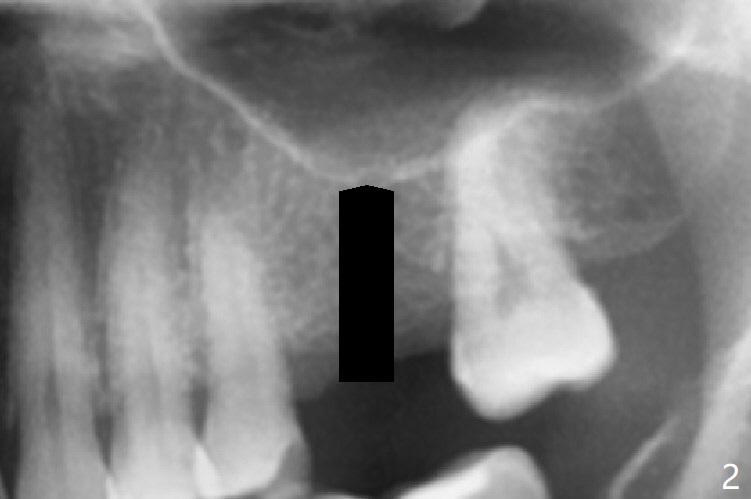

The guide is removed when the osteotomy at #14 (Fig.1 (8.45 mm bone height)) is finished in an under drilling manner in depth (Fig.2). The middle of the apical remaining bone is so thin (Fig.3 (white line representing the sinus floor)) that it can be pushed up like ping pong or eggshell (Fig.4 arrow). A 5x8.5 mm implant is placed with satisfactory insertion torque and depth, followed by insertion of a 6x3 mm healing abutment (Fig.5). There is mild resorption of the sinus floor distally 3.5 months postop, although the implant remains stable (Fig.6).